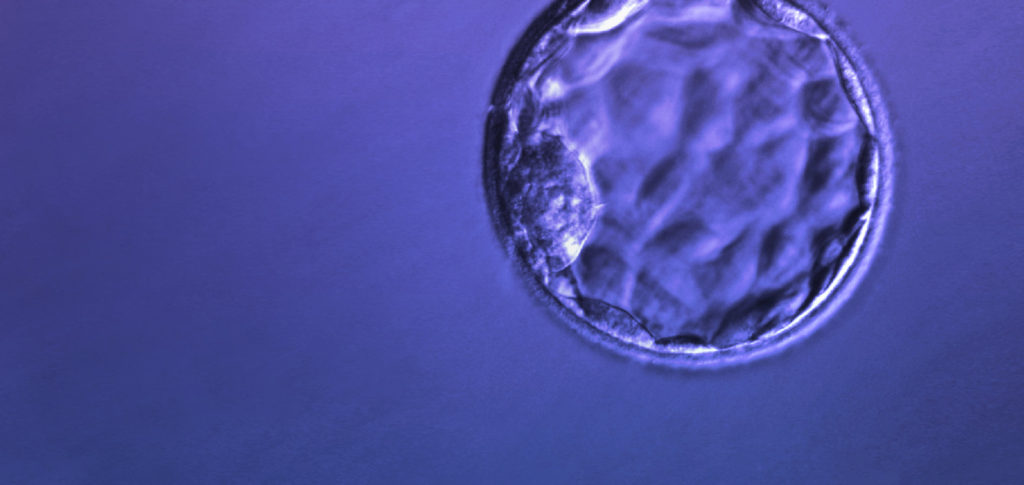

The ability to select one embryo for a transfer with the highest potential for implantation has been greatly enhanced by genetic analysis referred to as Comprehensive Chromosomal Screening or (CCS). A CCS-tested embryo can produce pregnancy rates identical to the transfer of 2 untested embryos, but without the risk of multiple gestations. Moreover, the combination of CCS and eSET reduces miscarriage rates and the number of attempts needed to achieve success through IVF. There is no doubt that RMANJ’s strategy and success with eSET has set the bar for IVF technology in the 21st century.